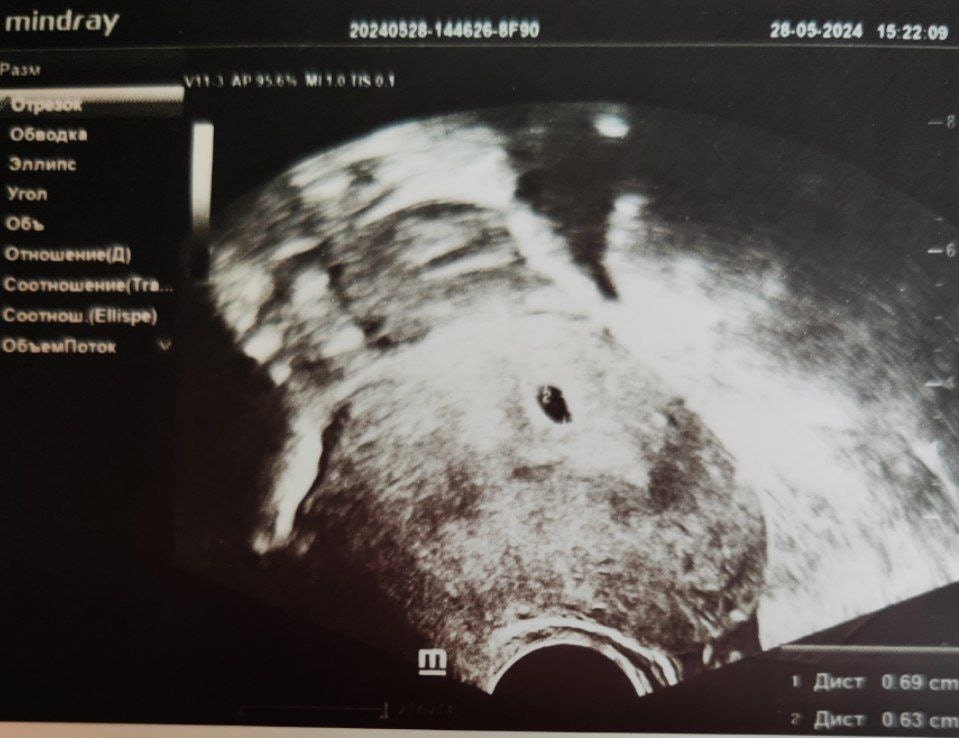

4 недели 6 дней, самое первое УЗИ (28.05.2024)

Средний диаметр ПЯ (плодного яйца) 6.6мм, ЖМ (желточный мешок) 1мм